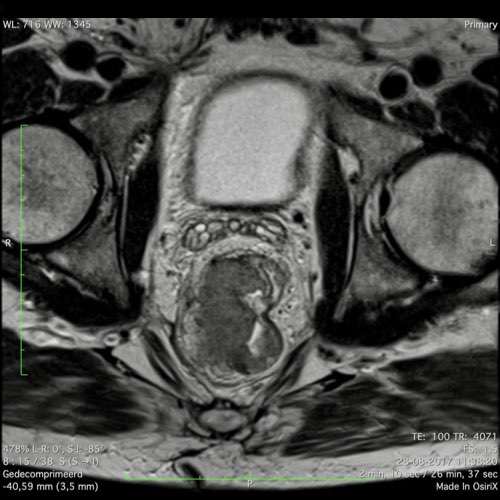

Hình ảnh

Các hình ảnh được cung cấp cho thấy ung thư biểu mô tế bào nhẫn với tình trạng dày lan tỏa thành trực tràng, hình ảnh bia bắn điển hình, và sự xâm lấn mỡ mạc treo trực tràng.